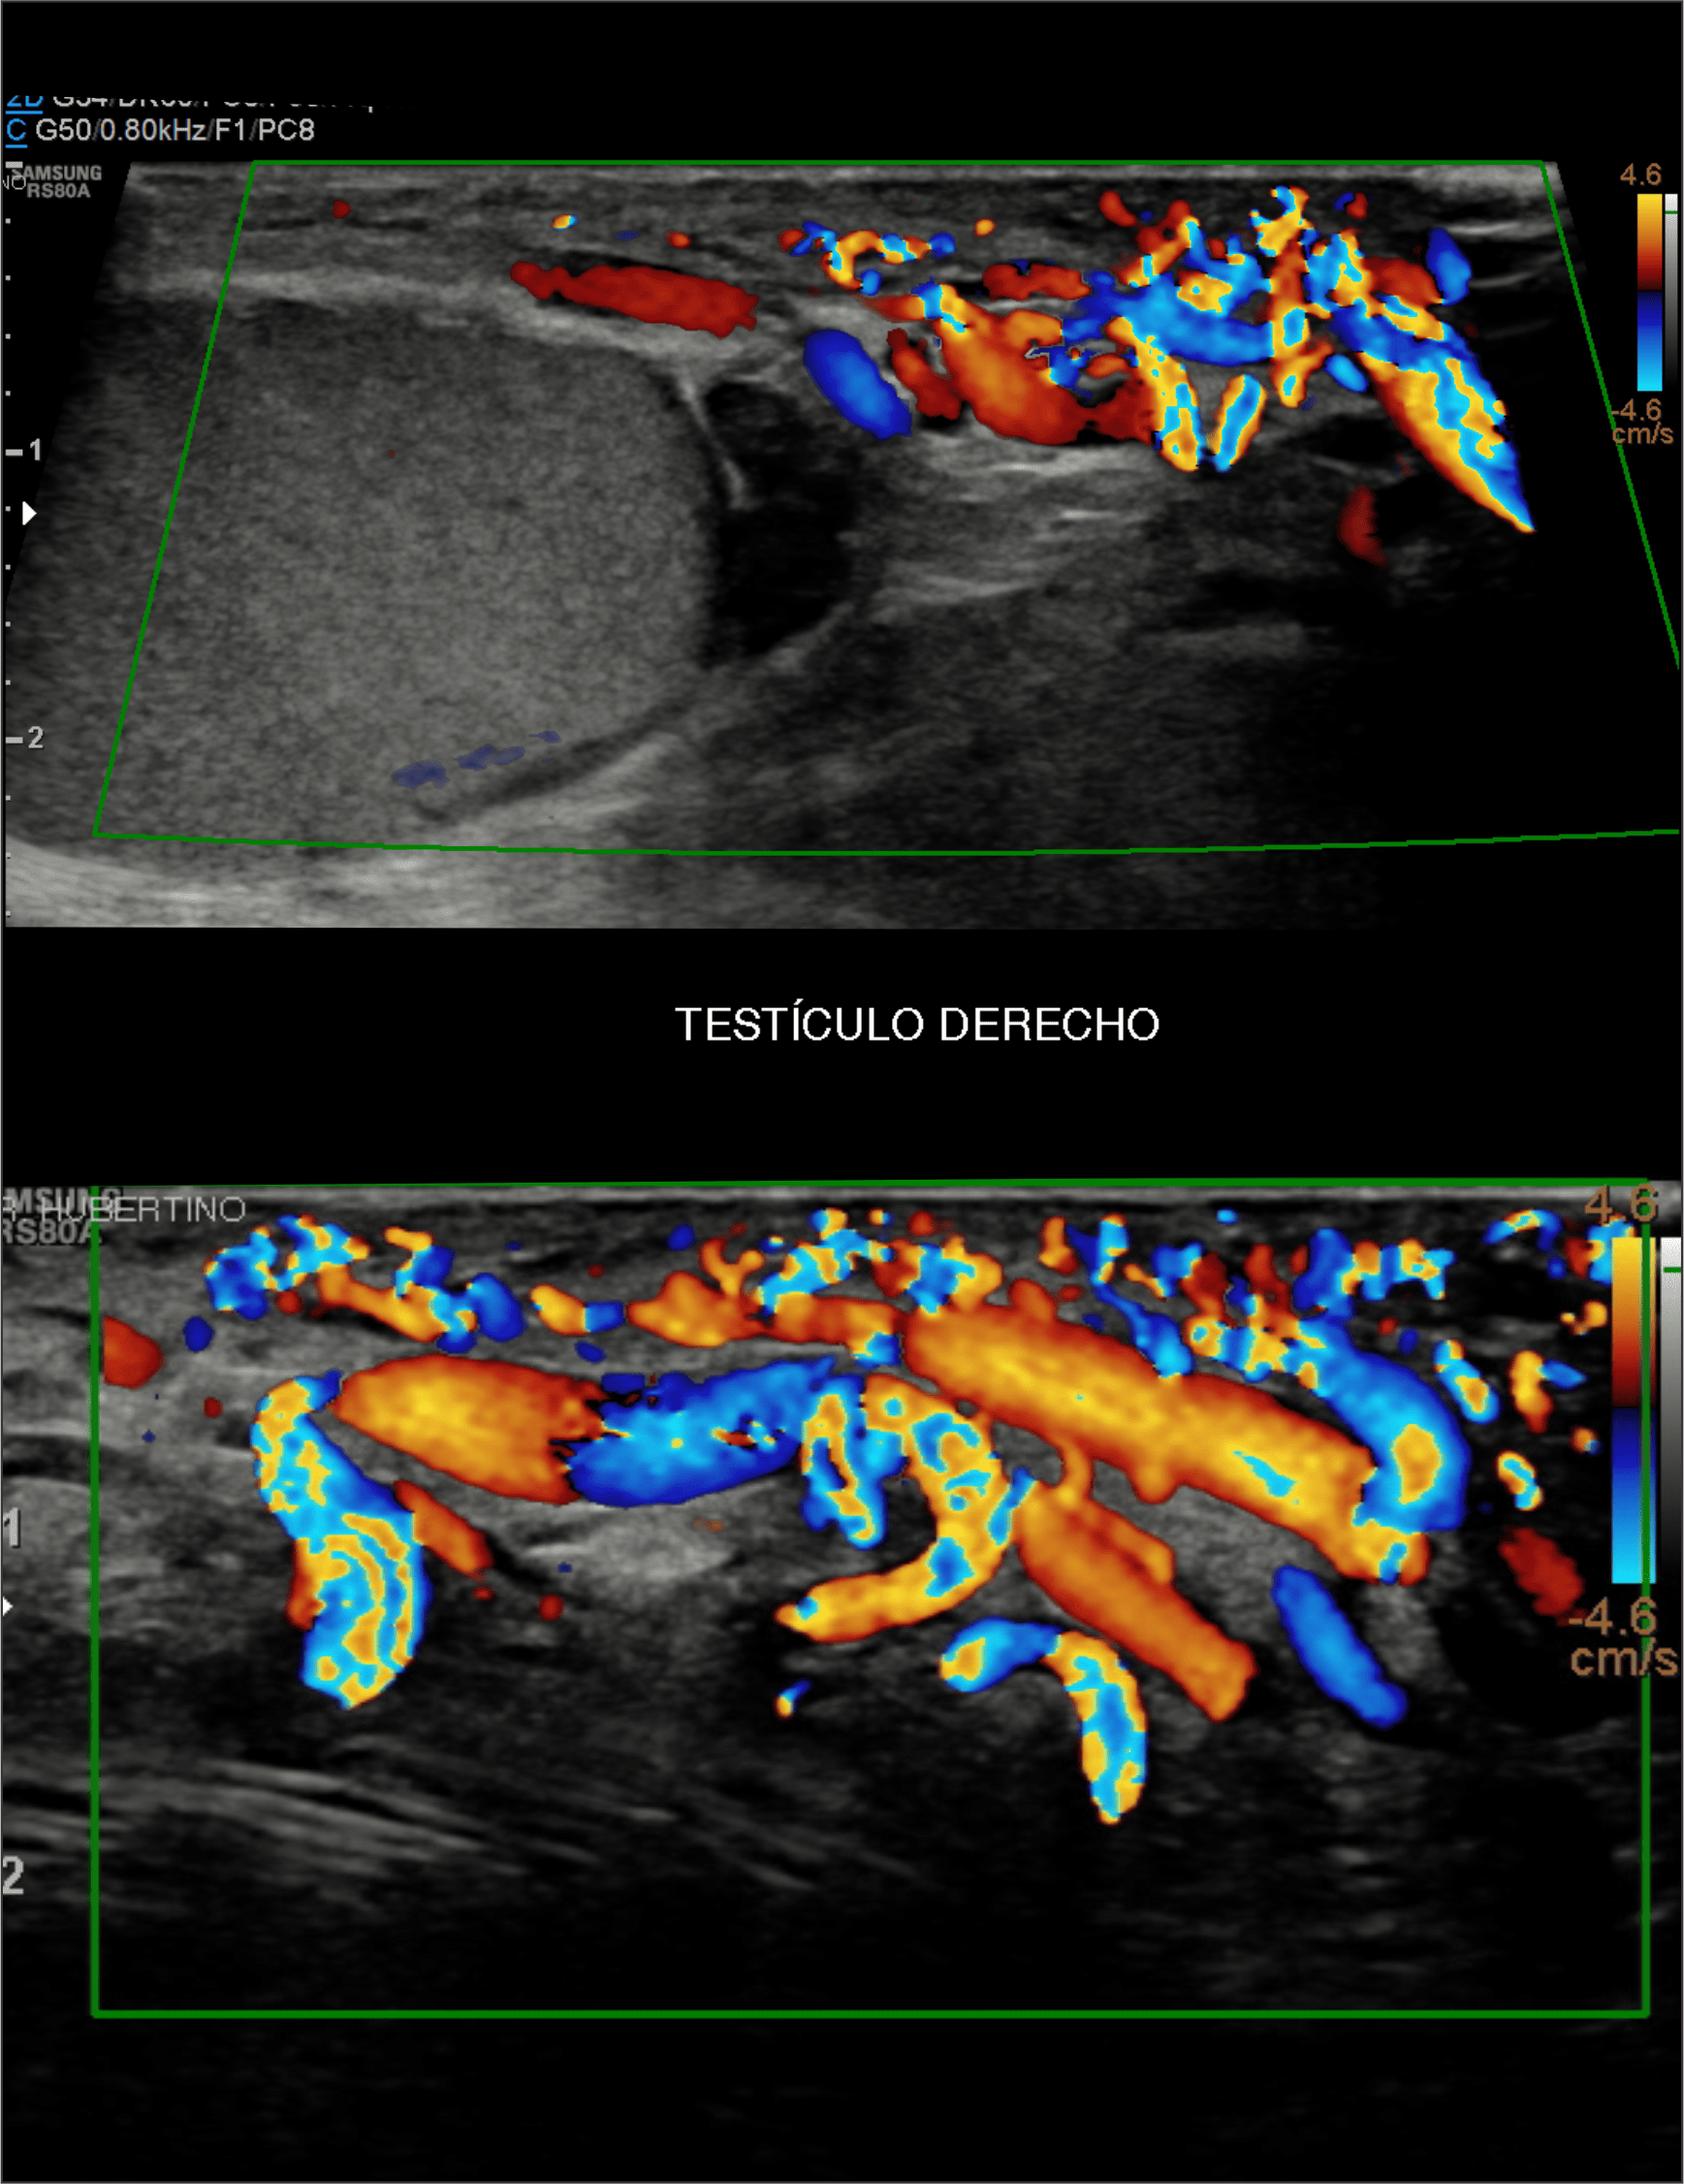

En Diagnoimagen incorporamos un enfoque de ecografía multiparamétrica, combinando modo B, Doppler color, Doppler de microflujo y elastografía, lo que nos permite una evaluación más completa y precisa en múltiples patologías.

🔹La ecografía Doppler permite evaluar el flujo sanguíneo en arterias y venas, siendo fundamental para el diagnóstico de insuficiencia venosa, várices, trombosis, estenosis carotídea y patología hepática.